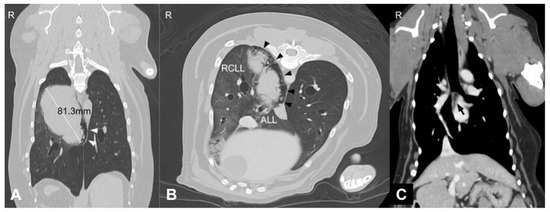

Computed Tomographic and Ultrasonographic Features in Three Dogs with Infected Uterus Masculinus and Concurrent Genital Neoplasia

Uterus masculinus is a rare disorder of sexual development in males, characterized by the presence of tubular female genitalia. Diagnostic imaging reports of infected uterus masculinus are limited. We describe the ultrasonographic and computed tomographic findings in three dogs, all presenting with abdominal [...] Read more.

Uterus masculinus is a rare disorder of sexual development in males, characterized by the presence of tubular female genitalia. Diagnostic imaging reports of infected uterus masculinus are limited. We describe the ultrasonographic and computed tomographic findings in three dogs, all presenting with abdominal distension, pain, and systemic infection. Imaging consistently revealed a fluid-filled, bicornuate structure arising from the prostate. In two dogs, the horns extended through the inguinal rings to the scrotal testes; in the third, with a prior left orchiectomy, both horns were intra-abdominal, the right ending in a peritoneal mass. Surgery and histopathology confirmed infected uterus masculinus, with Escherichia coli isolated from urine in all dogs and from the structure in two. Two dogs had Leydig cell tumors, one with concurrent uterine neoplasia; the third had an ovarian or ovotesticular granulosa cell tumor. Although rare, infected uterus masculinus is potentially life-threatening and should be considered in male dogs with abdominal pain, distension, or systemic infection. This is the first case series describing combined ultrasonographic and tomographic features of infected uterus masculinus, including novel findings such as cervix-like mural narrowing and fluid–fluid levels. It is also the first imaging description of an ovarian or ovotesticular tumor in a dog with uterus masculinus. Full article

Pulmonary adenocarcinoma in dogs, particularly in advanced stages, carries a poor prognosis with limited therapeutic options. Immunotherapeutic approaches that activate natural killer (NK) cells may provide additional clinical benefit. This report describes the clinical response and survival outcome of a 9-year-old neutered male [...] Read more.

Pulmonary adenocarcinoma in dogs, particularly in advanced stages, carries a poor prognosis with limited therapeutic options. Immunotherapeutic approaches that activate natural killer (NK) cells may provide additional clinical benefit. This report describes the clinical response and survival outcome of a 9-year-old neutered male Welsh Corgi with late-stage pulmonary adenocarcinoma treated with combined chemotherapy and cytokine-based NK cell-activating immunotherapy. The dog presented with intermittent coughing, dyspnea, and cyanosis. Imaging revealed a large pulmonary mass with suspected nodal metastasis (stage III, T4N1M0). Cytology confirmed pulmonary adenocarcinoma. A splenic myelolipoma, unrelated to the primary pulmonary tumor, was identified incidentally and surgically removed. Treatment included vinorelbine-based chemotherapy and cytokine-based immunotherapy using interleukin (IL)-15, IL-12, IL-23, and selenium. After temporary discontinuation due to adverse events, cytokine monotherapy was administered, followed by resumed combination therapy upon stage IV progression with contralateral lung metastasis. Radiographic follow-up demonstrated disease stabilization during monotherapy and prolonged survival with combination therapy. The dog survived for 241 days, including 143 days after stage IV diagnosis, exceeding previously reported outcomes. Although NK cell function was not directly evaluated, these findings raise the possibility that cytokine-based NK cell immunotherapy, when combined with chemotherapy, could have contributed to disease control and prolonged survival in advanced canine pulmonary adenocarcinoma. Full article